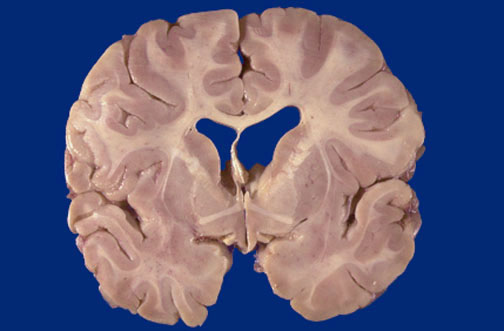

Identify the following regions of the normal brain in the image above: Anterior Commissure - Internal Capsule - Putamen - Globus Pallidus - Caudate Nucleus - Amygdala - Optic Tract Lateral ventricle Temporal lobe